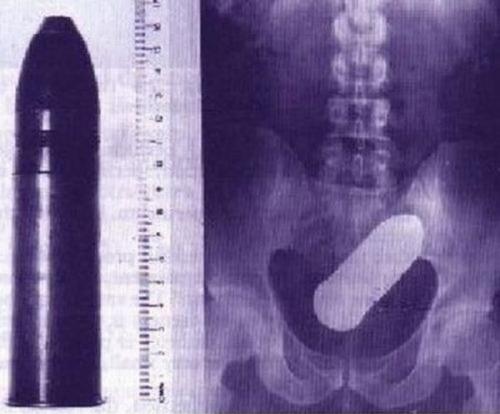

Предметы, которые можно обнаружить в человеке благодаря рентгену

Внутри человека с помощью рентгенологического оборудования можно обнаружить массу оригинальных предметов, причем порой даже несовместимых с жизнью.

Патрон